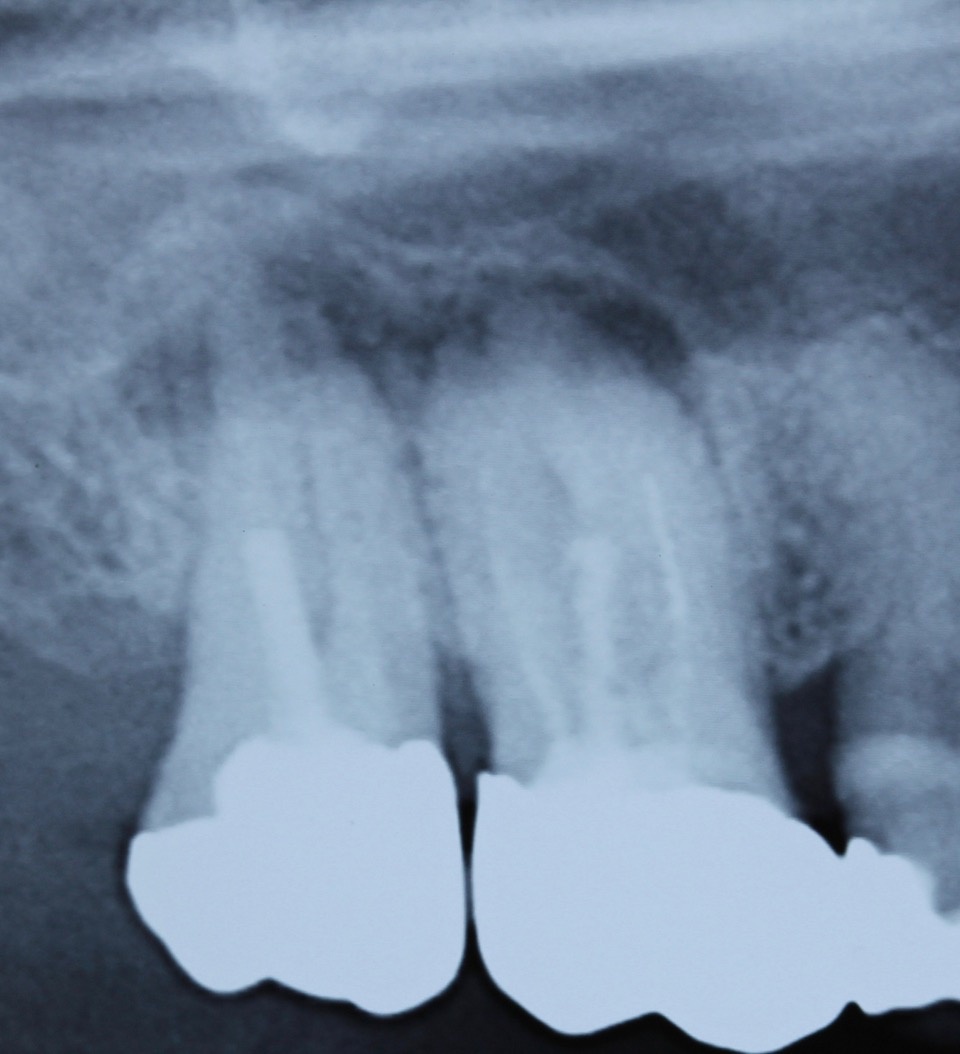

Ein nach Applikation des MTA angefertigtes Kontrollbild zeigt den suffizienten apikalen Verschluss der Konstriktion in einer Schichtstärke von etwa vier Millimeter (Abb. 2). Gleichzeitig wird in der Aufnahme die ausgedehnte Kanalstruktur des Zahnes 47 deutlich.

Im zweiten Schritt wurde durch plastisch erwärmte Guttapercha im Sinne der Back-Fill-Phase das Kanalsystem vollständig gefüllt und der Zahn anschließendadhäsiv verschlossen (Abb. 3). Zwölf Monate nach der Revisionsbehandlung ist die Patientin weiterhin beschwerdefrei und die Kontrollaufnahme zeigt den deutlichen Rückgang der apikalen Osteolyse (Abb. 4).